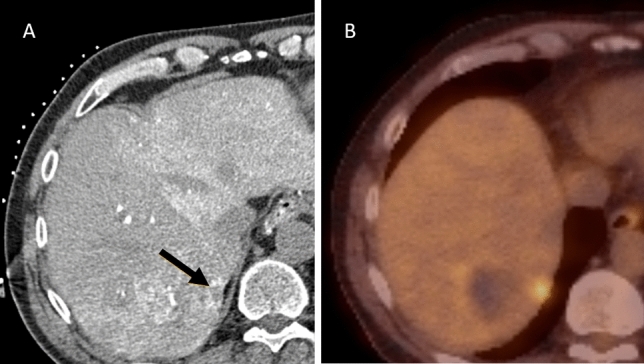

Fig. 2.

Case with concomitant CRLM: A and B; pre-procedural contrast-enhanced CT and 18F-FDG PET-CT. C: pre-procedural MRI (DWI). D: transcatheter CTHA in arterial phase. An additional ring-enhancing lesion in segment II (arrow) was found intra-procedurally. This lesion was considered highly suspect for CRLM and consequently ablated in the same procedure. This lesion was not detected with the conventional pre-procedural diagnostic modalities